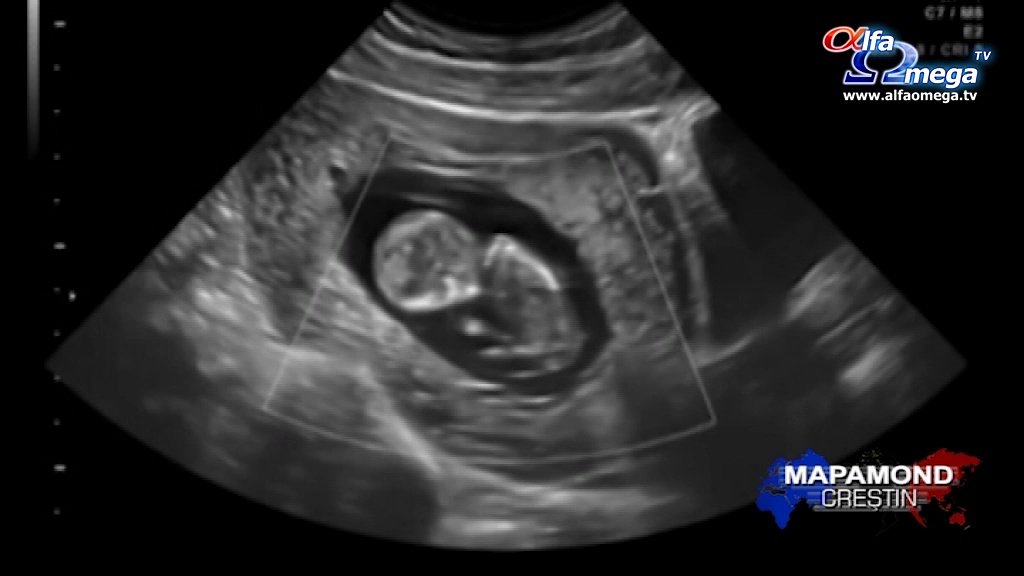

``În momentul în care l-am văzut și i-am auzit inima bătând am început să plâng``, spunea Richelle Scott.

``De obicei încep să plângă în timpul ecografiei, își acoperă ochii, dar pe parcurs încep să-l privească. Le spunem că ele sunt mame și că poartă în pântec un bebeluș. Le arătăm cum își suge degețelul, cum sughite. Acestea ajung să zâmbească și să plângă în același timp``, spunea Christine Melchor.

Park spunea că puterea acestui moment, acela de a ajuta o femeie însărcinată să-și înțeleagă noua identitate și existența bebelușului, nu poate fi subapreciată. Park și ceilalți membrii ai echipei petrec timpul necesar cu noile mămici.